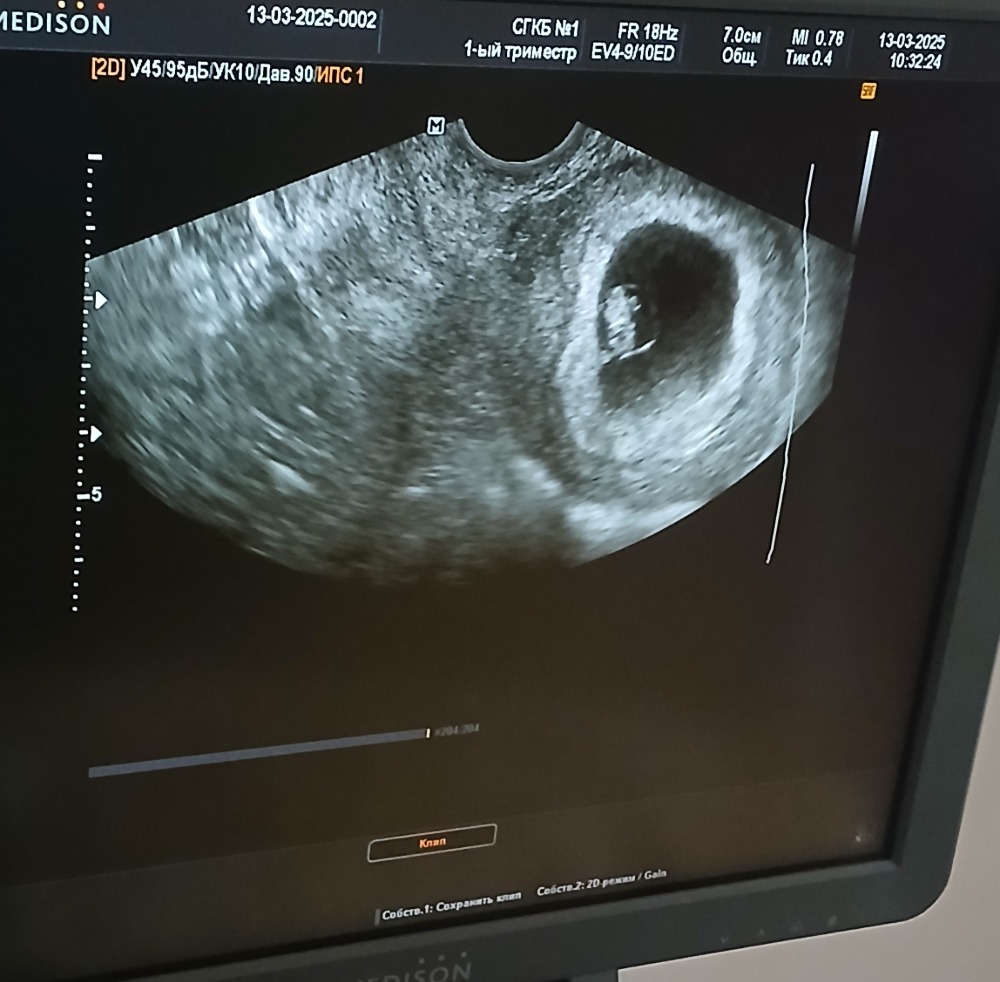

в Зачатие 9 месяцев

Повторное УЗИ в больнице

13.03.2025